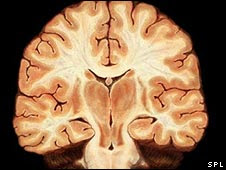

Scientists from Gladstone Institute of Neurological Disease and the University of California looked at fatty acids in the brains of normal mice and compared them with those in mice genetically engineered to have an Alzheimer's-like condition.

They identified raised levels of a fatty acid called arachidonic acid in the brains of the Alzheimer's mice.

Dr Rene Sanchez-Mejia, who worked on the study, said: "The most striking change we discovered in the Alzheimer's mice was an increase in arachidonic acid and related metabolites [products] in the hippocampus, a memory centre that is affected early and severely by Alzheimer's disease."